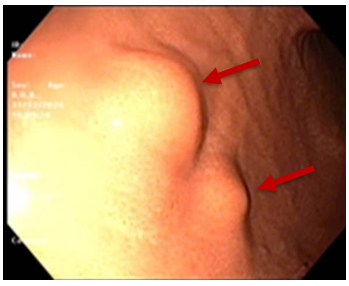

UNG THƯ DẠ DÀY KHỞI PHÁT SỚM

Theo Globocan 2022, ung thư dạ dày đứng thứ 5 về tỷ lệ mắc và tỷ lệ tử vong, với 968 784 ca mắc mới và 660 175 ca tử vong. Bệnh tiến triển thầm lặng, các triệu chứng ban đầu  thường mơ hồ và không đặc hiệu dễ nhầm lẫn với các bệnh lành...